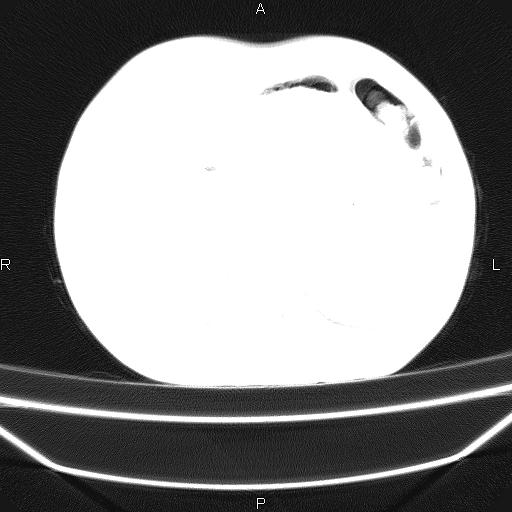

患者,男,40岁。间断发热,咳嗽二十余日。体温最高达38.9° 在当地诊所抗炎治疗三天后体温降至正常,患者自行停药。今又发热。胸片示,左下肺阴影。

左下肺片状高密度影,境界模糊,密度不均,考虑感染性病变可能性大,建议抗炎治疗后复查。左肺门增大,不除外占位性病变,必要时支气管镜检。

考虑感染性病变可能性大,抗炎后复查,占位不排除。

建议强化或纤支镜观察,考虑肿瘤性病变可能性大